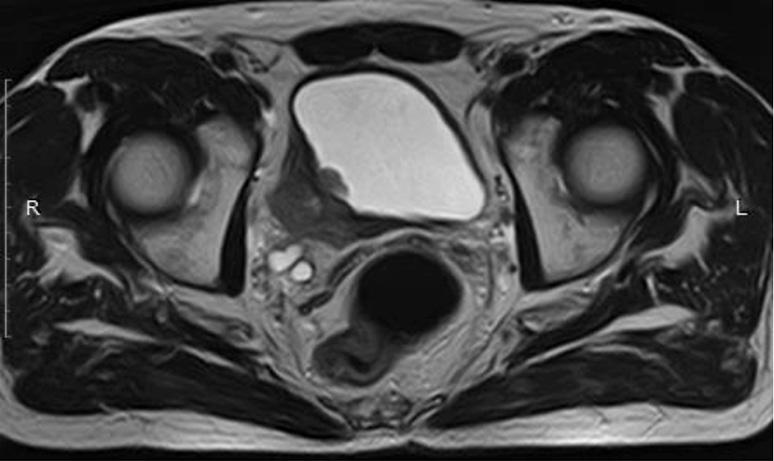

Рис. 5. МРТ ОМТ от 27.12.2021 в сравнении с МРТ от 24.03.2022. Состояние после 6-го курса лекарственного лечения по схеме EP: отсутствие опухолевого роста.

Fig. 5. Pelvic MRI dated 27.12.2021 in comparison with MRI dated 24.03.2022. State after the 6th course of drug treatment according to the EP regimen: no tumor growth.

Пациенту Н. с 11.2021 по 03.2021 проведено 6 курсов АПХТ по схемe EP. По результатам контрольного обследования отмечена выраженная положительная динамика в виде отсутствия опухолевого роста перивезикально и в полости мочевого пузыря (МРТ ОМТ от 24.03.2022); рис. 4, 5. Очаговые изменения костей скелета без динамики (сцинтиграфия скелета от 25.03.2022). Онкомаркеры (27.12.2021): винилминдалевая кислота – 5,3; гомованилиновая кислота – 5,8; 5-оксииндолуксусная кислота – 4,5, хромогранин А – 0,96; нейронспецифическая енолаза – 13,48; серотонин – 29,7. Учитывая выраженный положительный эффект на фоне ранее проводимого лечения, морфологическую структуру опухоли, рекомендована монохимиотерапия (МХТ) препаратом этопозид (100 мг 1–10-й дни, курс 21 день) до прогрессирования или неприемлемой токсичности с контрольным обследованием через 3 курса.

В июне 2022 г. выполнено контрольное обследование, МРТ ОМТ: на полученных МРТ в сравнении с обследованием от 24.03.2022 без существенной динамики. Пациент оставлен на МХТ препаратом этопозид (рис. 6).

Рис. 6. МРТ ОМТ от 07.06.2022. Состояние после 6-го курса лекарственного лечения по схеме EP. Cостояние в процессе МХТ препаратом этопозид.

Fig. 6. Pelvic MRI dated 07.06.2022. State after the 6th course of drug treatment according to the EP regimen. Monochemotherapy with etoposide is ongoing.